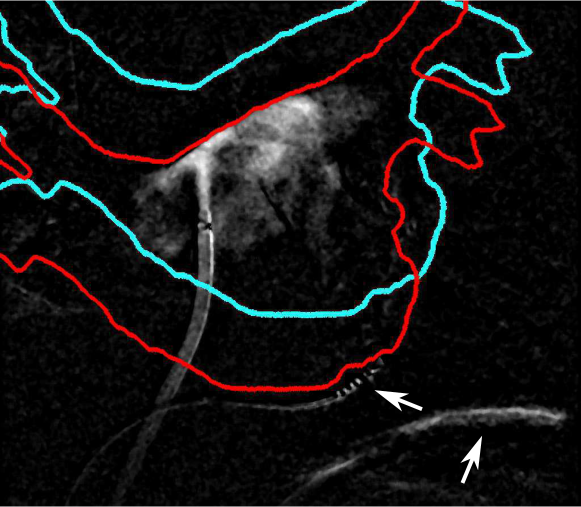

Refer to caption

Figure 1: A correct (red) and wrong (cyan) registration result. In both cases, the contrasted area is fully inside the projection shadow represented by the colored outline. This leads to a similar NCC value when using only an area-based feature for automatic registration. Thanks to the best reference frame selection, motion artifacts could be kept to a minimum. Only some remained in the vicinity of the moving coronary sinus (CS) catheter and the diaphragm, see white arrows.